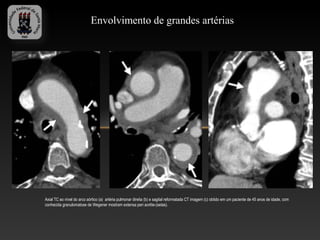

Envolvimento de grandes artérias

Axial TC ao nível do arco aórtico (a) artéria pulmonar direita (b) e sagital reformatada CT imagem (c) obtido em um paciente de 45 anos de idade, com

conhecida granulomatose de Wegener mostram extensa peri aortite-(setas).